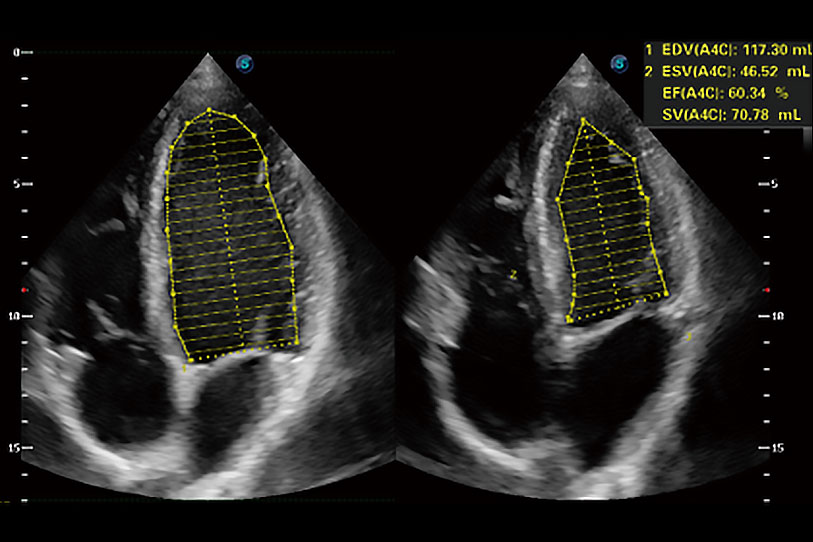

能夠基于左心室壁追蹤和辛普森法,自動計算射血分?jǐn)?shù),支持多個可移動點(diǎn)描跡,與手動測量相比,極大節(jié)省了動物醫(yī)生的時間和精力。